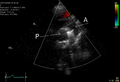

An echocardiogram of a stented persisting ductus arteriosus: One can see the aortic arch and the stent leaving. The pulmonary artery is not seen.

An echocardiogram of a coiled persisting ductus arteriosus: One can see the aortic arch, the pulmonary artery, and the coil between them.